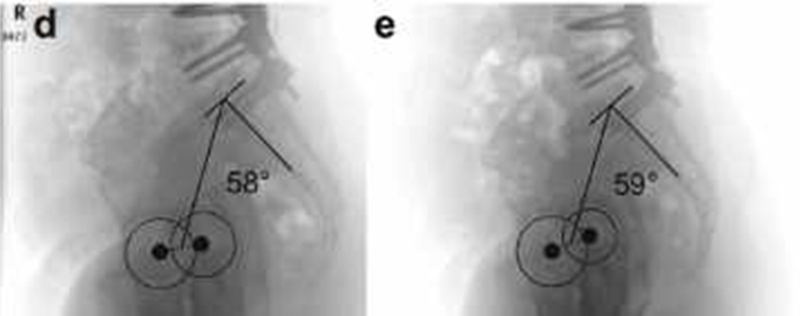

六、PI本身并非固定不变的参数

最近一些文献指出,PI可能不是一个固定值。Lee等研究了11名接受骨盆固定,18名未固定到骨盆的ASD患者,发现两组术后即刻PI较术前均有显著增加,并且未行骨盆固定的一组在术后随访过程中,PI持续增加,这可能与LL矫正,骨盆形态恢复后骶髂关节间剪切应力增大有关(图5)。

尽管术后PI作何变化仍有争议,但这些研究结果提示,PI可能会受手术影响。因此,PI-LL=±9°这一默认PI不变,而根据术前PI预测术后需要获得的LL的公式是值得商榷的。

图5. 骨盆固定和不固定对PI的影响